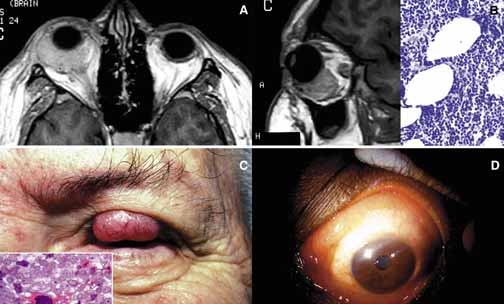

Fig. 11 Sarcoidosis. The appearance of a large sarcoidosis granuloma involving the anterior orbit and periorbital skin (g). The central dome-like lesion is caused by secondary to a Staphylococcus infection. In addition, plaquoid skin lesions of sarcoidosis are seen above the left eyebrow, on the left upper eyelid, and on the periorbital skin (A). The T2-weighted axial MRI with contrast reveals bilateral enlargement of lacrimal glands (g) in another case B. Frames C and D show T1-weighted sagittal MRIs with localized granulomatous masses of sarcoidosis within the posterior orbit involving the apex and extending into the cavernous sinus (C, D). A well-delineated but not encapsulated mass of a sarcoid granuloma (E). The histopathology of sarcoidosis consists of multiple granulomas composed of histiocytic cells, chronic inflammatory cells, and multinucleated giant cells (g) (F).

Approximately one-fourth of sarcoidosis patients develop ocular and orbital manifestations including anterior and posterior uveitis, chorioretinitis, conjunctival and eyelid granulomas and orbital mass lesions (Fig. 11). Lacrimal gland is a common site of involvement; autopsy studies show a high percentage of microscopic disease; however, only 15% to 20% of the patients show clinical symptoms. Although virtually any part of the orbit may be involved with sarcoidosis, the most common site is the lacrimal fossa and the disease in this location may be confused with chronic dacryoadenitis, Sjögren syndrome, or space-occupying lesion. Sarcoid granulomas may also extend into the orbit from adjacent sinus mucosa.116 If other manifestations of the disease are absent, these cases may mimic secondary orbital tumors and they can only be differentiated by biopsy.

The treatment of sarcoidosis is directed to the systemic disease. Surgery may be necessary to biopsy or debulk orbital lesions if there is a need for histopathologic evaluation in patients with no other easily accessible biopsy sites. In few instances, the orbital disease presents with no history or detectable symptoms of systemic sarcoidosis (Fig. 11). In these patients, sarcoidosis is usually a surprising diagnosis obtained from an orbital “tumor.” The mainstay of treatment is the use of systemic corticosteroids and antimetabolites such as methotrexate.